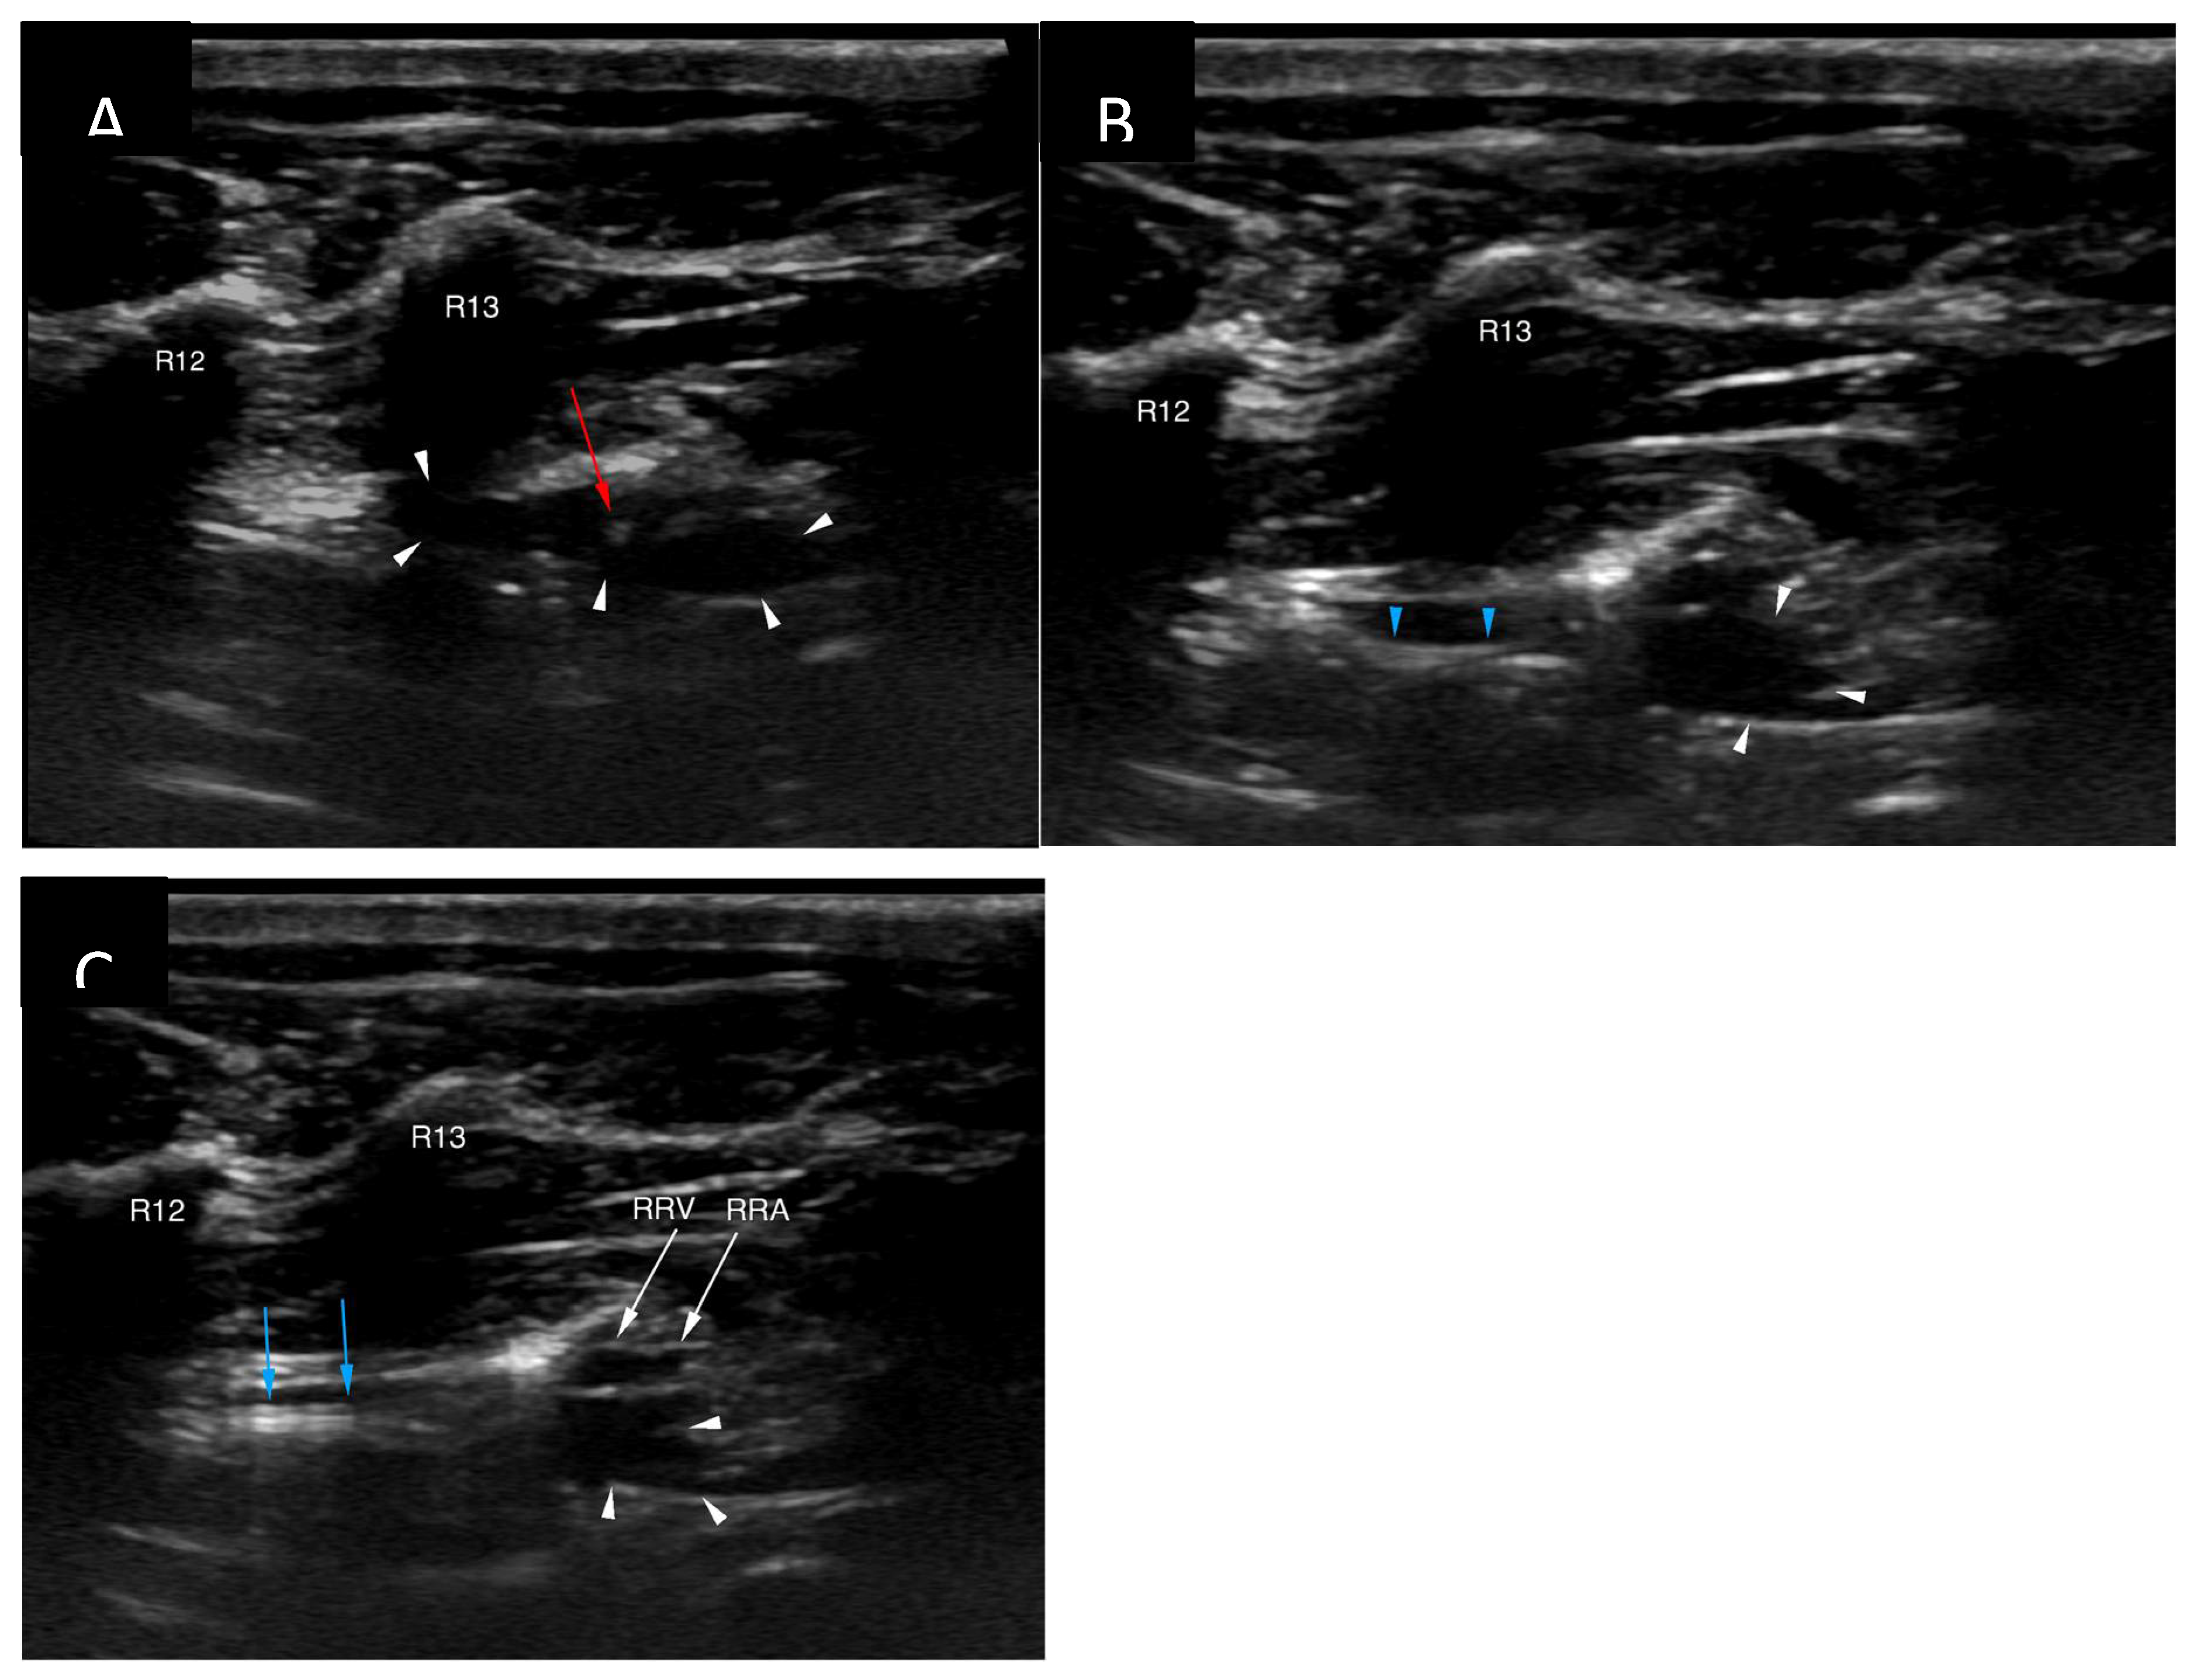

Figure 4. Ultrasound-guided percutaneous cisterna chyli access. The cisterna chyli is delineated with white arrowheads. (A) The needle tip (red arrowhead) has been positioned inside the cisterna chyli. (B) Insertion of the microguidewire (blue arrowheads) through the access needle followed by the microcatheter (panel C, blue arrows). Note the location of the right renal vessels (panel C, white arrows). R12 – twelfth right rib; R13 – thirteenths right rib; RRV – right renal vein; RRA – right renal artery.

The cisterna chyli was punctured with an 18G, five-centimetre-long vascular access needle (Merit Advance, Merit Medical) under ultrasonographic guidance (Logic S7, GE Healthcare). A 3.8-10.8 MHz linear transducer (11L, GE Healthcare) was used, and the needle trajectory was from caudal to cranial (Figure 4). Care was taken to avoid iatrogenic injury to the aorta and the right renal artery and vein. Although the initial puncture appeared successful, the combination of the 3.0 Fr microcatheter (Slip-Cath Infusion Catheter, Cook Medical) and a 0.014-inch guidewire (Runthrough NS, Terumo) could not be advanced into the central lymphatic system. The author suspects that either the initial access was lost when the ultrasound probe was removed from the patient's skin for fluoroscopic monitoring, or the angle of the initial puncture was too steep precluding easy advancement of the equipment. The CC access was repeated with a flatter angle and both the puncture as well as the advancement of the equipment were monitored only with ultrasound to minimize risk for needle displacement. On this occasion introduction of the guidewire followed by the catheter could be accomplished without problems (Figure 5).

To overcome the technical challenges mentioned by Singh et al. [20] the author decided to apply certain modifications. Ultrasound guidance was used to puncture the cisterna chyli and patient positioning and needle trajectory were inferred from the computed tomography study. The dorsoventral dimension of the CC was advantageous in this patient (Figure 2) and allowed for a relatively uncomplicated access, although great care needed to be maintained to prevent iatrogenic injury/laceration to the aorta and the right renal artery and vein (Figure 4). Ultrasound guidance provided real-time monitoring of the trajectory of the needle and continued fanning of the ultrasound probe allowed avoidance of the neighbouring vascular structures. No vascular sheath was used in this case to minimize number of exchanges and reduce the risk for loss of access. Instead, the microcatheter was inserted through the needle, a concept that is utilized during placement of epidural catheters.